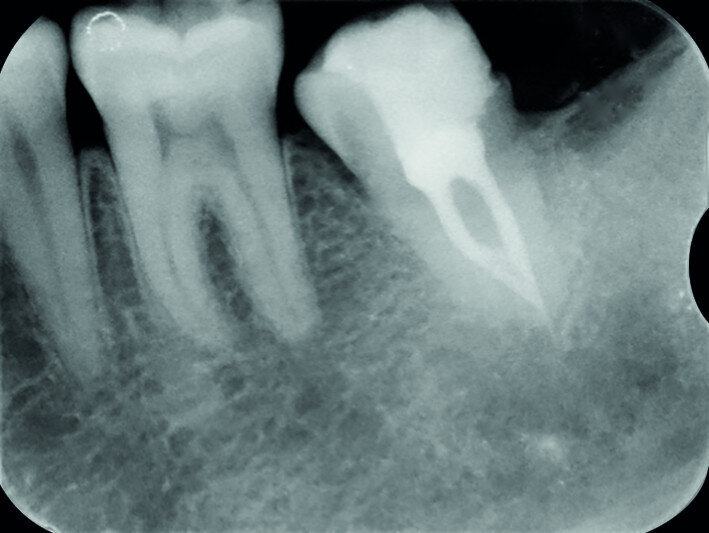

Fig. 15c: Radiograph: One-year recall.

The left mandibular second molar of a 35-year-old female patient had been compromised because of a vertical root fracture and a large periapical lesion was present. After explanation and informed consent, the treatment was scheduled. The right mandibular third molar was preferred as a donor to the left mandibular third molar because of a more compatible anatomy and for an easier stabilisation. After local anaesthesia of both the donor and the recipient sites with 2 per cent mepivacaine with 1:100,000 adrenaline, the left mandibular second molar was extracted and the alveolus debrided. Then the donor tooth was atraumatically extracted, quickly repositioned in the recipient site and stabilised with sutures at about 1.5–2.0 mm of infraocclusion. An antibiotic (amoxicillin/clavulanic acid, 1 g, by mouth twice a day for five days) and a non-steroidal anti-inflammatory drug (ibuprofen, 600 mg, by mouth twice a day for five days) were prescribed, along with rinses with 0.2 per cent chlorhexidine. The sutures were removed after two weeks and endodontic treatment was performed after three months. The periapical lesion healed and the tooth was fully functional after 12 years (Figs. 14a–d & 15a–d).